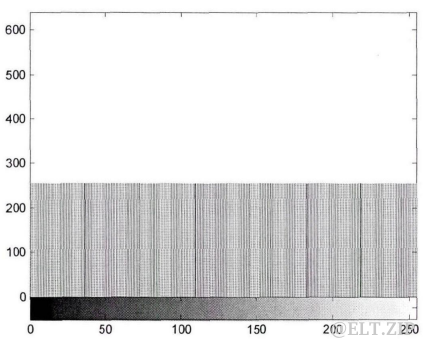

基于稀疏表示的医学序列图像压缩方法

- 随着医学影像技术的发展,近年来,各种医学影像设备产生了大量的医学数字图像。医学数字图像具有

内容丰富、形象直观的特点,能够很好地辅助医疗诊断。然而,因其数据量非常庞大,会占用大量的存储空间和传输带宽,所以有必要对医学数字图像数据进行压缩。 - 现有的图像压缩标准大都基于图像的正交变换,其中基于离散余弦变换的JPEG压缩标准最具代表性,JPEG算法具有优良的压缩性能,适用于各类图像的压缩。但是,JPEG算法使用固定的字典进行编码和解码,将其用于医学数字图像的压缩时,并

没有考虑到医学数字图像本身的特点进一步提高压缩性能。此外,正交变换对于图像的表示并不是最优的,它不能稀疏地捕捉图像的规则性和轮廓特征,因此进一步研究图像压缩的突破点在于图像的表示方面。 - 近几年,稀疏表示成为图像处理领域的研究热点。稀疏表示理论表明,任何信号可以在过完备原子库上稀疏地分解,即使用过完备原子库中尽量少的原子的线性组合来表示原始信号。图像在过完备原子库上稀疏分解的结果十分简洁,而且在直观上也很符合人眼的视觉特性。图像稀疏表示的优良持性,使其成为

解决医学数字图像压缩问题的新途径。

经过多年的研究,随着许多基于离散余弦变换和基于小波变换的图像压缩方法的诞生,图像压缩问题达到了一个重要的里程碑,同时也是个研究瓶颈。基于正交变换的图像压缩方法虽然能取得良好的压缩效果,但仍然存在一些不足之处,例如正交变换不能很好地表示出图像的轮廓,使用固定字典对医学数字图像压缩不会考虑医学图像自身的特点,压缩速率较慢等等。图像稀疏表示是近几年兴起的一种新的图像表示方法,基于稀疏表示的图像压缩为解决医学数字图象压缩问题提供了一种新的研究思路。

医学序列图像特点

-

医学序列图像是指在相同的成像设备下,对同一研究对象,在不同断层的扫描切片集合或不同时间的扫描切片集合。根据切片集合的不同来源,可分为

时间序列图像和空间序列图像。时间序列图像是指患者延时间轴获得的图像集,记录患者在一段时间内的病患信息,例如,一位SARS病人在发病期间,每天都要拍摄胸腔CT影像,这些在时间上离散的影像,就构成了一组相同类型的医学时间序列图像。空间序列图像是指成像设备对病人某个器官的不同断层的扫描切片,利用这些连续的扫描切片,通过三维重建技术,将人体器官以“三维”的形式真实地显示出来,实现其三维可视化。

医学序列图像有其自身的特点,即背景比较单一,序列中相邻的图像包含的大部分信息是相同的, 也就是说表示这些图像会存在大量的重复信息,图三展示了展示了某个病例的部分颅脑 CT 图像序列,可以看出,这些图像序列是渐变的,即

相邻图像的变化很小。因此,本文提出的基于稀疏表示的医学序列图像压缩方法,就是首先减少序列图像之间的相关冗余信息,然后采用稀疏表示的方法压缩图像数据,从而达到图像压缩的目的。

基于稀疏表示的压缩方法

- 从医学序列图像(图三)的特点可以看出,序列中

相邻图像存在很强的相似性,若将图像划分为指定大小的图像块,在这一系列的图像块中,会存在很多相似的图像块。 - 基于此,本文提出基千稀疏表示的医学序列图像压缩方法,首先将一例序列图像分块,然后根据所有图像块之间的相似性,选择一些图像块作为基准块,就是说,其他的图像块与基准块集合中的某一块非常相似,可直接用该基准块来代替。在进行相似性衡量之时,一一记录下所有图像块与基准块之间的对应关系。然后只用对基准块集合进行

稀疏分解,将基准块集合分解得到的稀疏系数矩阵作为二次字典。 - 待表示的信号是稀疏表示模型中字典的某几列的线性组合,而这里的二次字典,待表示的信号仅仅根据二次字典的某一列来重建,且不要求二次字典的过完备性。图像压缩过程中,由一系列的图像块计算相似性后,对一组互为相似的图像块只用考虑其中一个,并将其设为基准块,其他的图像块则被认为是副本,副本不用存储。对于所有的图像块,需要依次为每个图像块存储与之相似的基准块的序号,即

参考索引。基准块的序号和二次字典的列号是一一对应的,也就是说需要指明在图像块重建时,它是使用二次字典中哪一列的系数来重建。

此算法分为两部分:

- 二次字典,字典中的每一列为稀疏系数向量,采取逐列存储的方式,列中的数据为稀疏系数,每个系数分别存储

位置索引和幅值两个信息; - 参考索引,因为参考索引其实就是

二次字典的列号,而二次字典的列数就是基准块的数量,假设相似性计算之后得到N个基准块,则参考索引的数据范围是O~N-1。

算法测试

- 将上述提出的基于稀疏表示的序列图像压缩方法与传统的基于稀疏表示的图像压缩方法、JPEG 压缩方法作对比,图六展示了这几种不同方法的压缩效果。可以看出,本文方法的压缩效果优于传统的基于稀疏表示的图像压缩方法,在

低比特率时 JPEG 压缩效果优于本文方法,在高比特率时该方法压缩效果优于JPEG。考虑到医学图像对图像质量要求很高,也就要求其峰值信噪比较高,基于稀疏表示序列图像的方法在高峰值信噪比的情况下,能够达到优于JPEG的压缩效果。

图六.不同压缩方法的压缩效果比较

总结

- 本文介绍了基于稀疏表示的医学序列图像压缩方法,该方法利用医学序列图像之间的相似性,建立了二次字典和参考索引,实验结果表明,++这种对序列图像进行整体压缩的方法在高峰值信噪比时其压缩效果优于 JPEG 压缩标准++。